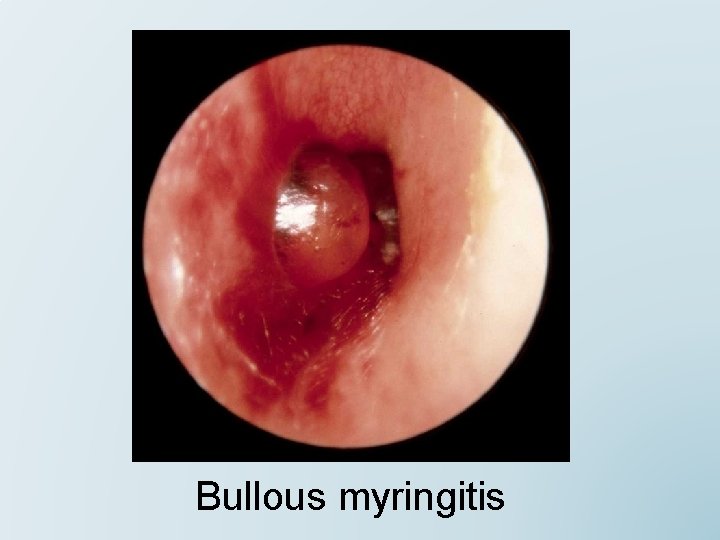

Extrapulmonary Manifistations Legionella Bradycardia Hyponatremia Diarrhea: 20% Mental confusion Glomerulonephritis Bullous myringitis Mycoplasma (painful haemorrhagic blisters on the ear-drum and external auditory canal) Splenomegaly Lymphadenopathy Maculopapular skin rash

Bullous myringitis